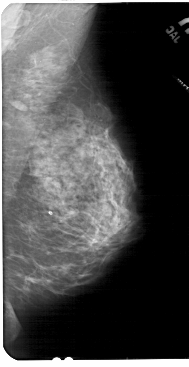

A_1842_1.RIGHT_CC

RIGHT_CC LINES 5446 PIXELS_PER_LINE 2656 BITS_PER_PIXEL 12 RESOLUTION 43.5 NON_OVERLAY